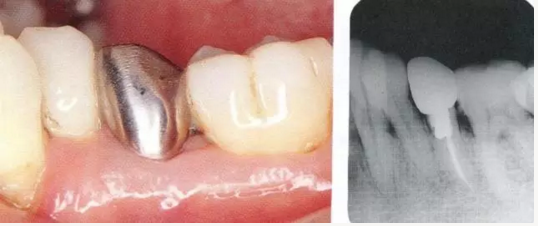

2222.png

▲圖18-1,2

▲圖18-1  左下5佩戴金屬冠,但是由于近遠(yuǎn)中接觸點(diǎn)的位置和大小不合適,導(dǎo)致鼓形間隙基本消失。

▲圖18-2  同部位的X光片??梢钥吹烬l下有牙結(jié)石沉積,并且有牙槽骨吸收現(xiàn)象。